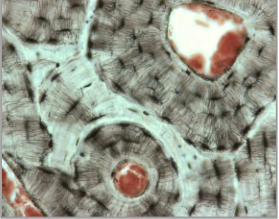

What type of bone is this?

Lamella bone

Made slowly

Organised

Layered structure

Name the following cells

Osteocytes - stellate, entombed in bone

Osteoclast - multinucleated

Bone

Osteoblast - plump & cuboidal

Lining cells - difficult to see, flattened and line the bone